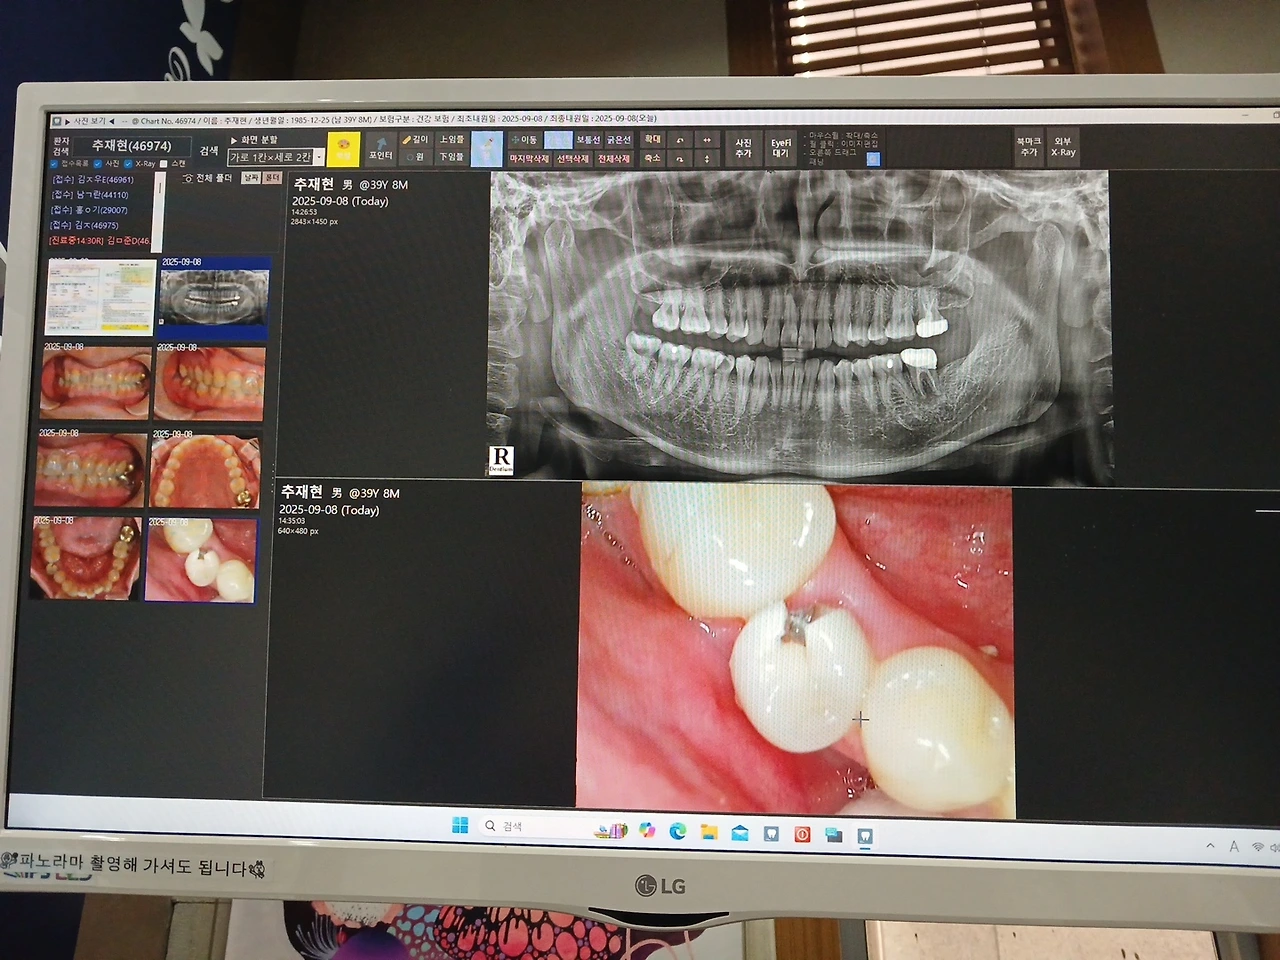

그러다가 내 오른쪽 치아 아래 송곳니에 구멍이 생겨 치과에 가는 일이 생겼다.

속이 크게 비어 양끝만 간신히 남아 있는데 신경치료 하고 속을 채운다 해도 오래 쓰지 못한다는 진단.

구멍 난 송곳니 뽑고 임플란트 새 이빨을 인공적으로 심기로 하였다.

치료를 하려면 내 치아 상태를 제대로 알아야 한다.

다양한 각도에서 사진을 찍어둔 걸 보여주며 간호사와 원장님은 지금 나의 상태를 알려주셨다.

"스케일링은 한 번도 안 받으셨다고요? 그러면 안 돼요. 6개월에 1번은 받아야 좋은데 세균이나 염증을

막아주는 역할을 해줘요. 오른쪽 어금니 금니 씌우신대 보면 검게 변했죠 염증이 시작되고 있어요.

전체적으로 치아 충치들이 조금씩 보이는데 아직은 관리 잘하시면 괜찮아요.

오른쪽 위에도 약간 구멍 생긴 게 하나 보이는데 초기라 신경치료 하고 국가에서 지원하는 재료로

때우면 저렴하게 하실 수 있을 것 같아요."